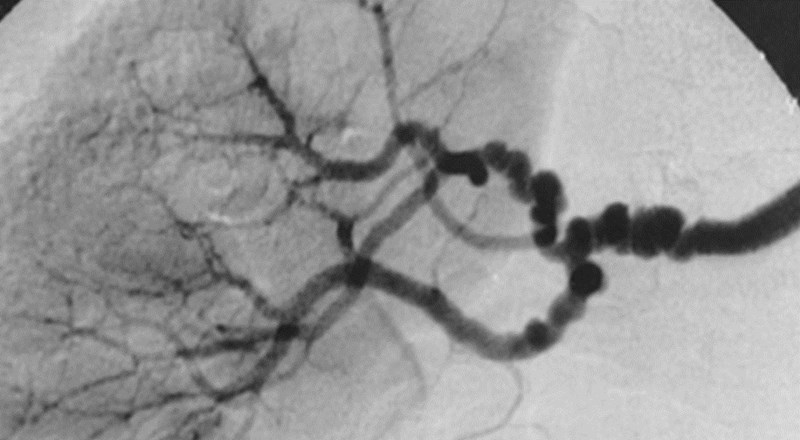

Young patient presents with hypertension. Angiography shows a “string of beads” appearance of the renal artery.

Fibromuscular Dyplasia

What are some causes of hypertension?

90% is primary (essential) and related to increased cardiac output or total peripheral resistance.

Remaining 10% mostly secondary to renal disease, including fibromuscular dysplasia in younger patients.